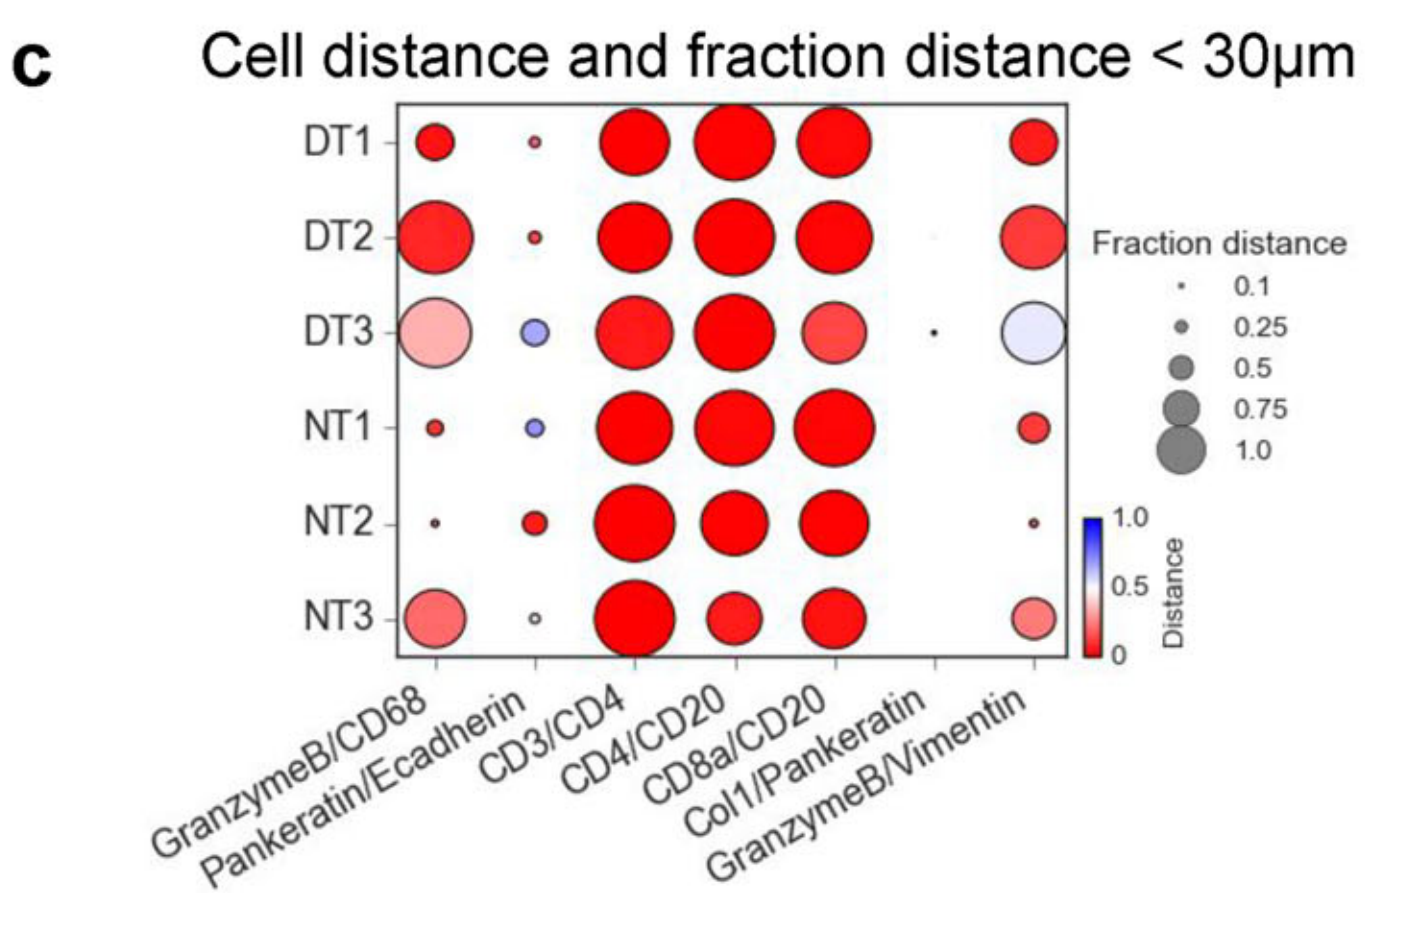

Allam et al., 2021

Spatially visualized single-cell pathology of highly multiplexed protein profiles in health and disease

Condition Dimension

Categorical

Data

Modality

Imaging-based

Resolution of observation

Cellular

Visualized Elements

ObservationRelationshipStatistic

Biological

MolecularSystemic/IntegrativeTissue

Abstraction

NonePartial

Chart Type

Dot ChartFlourescence tissue imageScatterplot

Communicative/Contextualization

AnnotationHighlighting

Comparative Design

Explicit encodingJuxtaposition

Layout

LinearSpatial : Physical

Scalability Strategy

Sampling/Filtering

What is the spatial localization and expression correlation between markers in both healthy and diseased tissues?